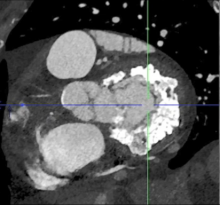

Mitral valve replacement (MVR) in patients with mitral annular calcification (MAC) poses a significant surgical challenge. A direct transatrial transcatheter mitral valve replacement (TMVR) approach with resection of the anterior leaflet of the mitral valve has been described (1, 2). Patients with MAC usually have small hypertrophic ventricles at risk of left ventricular outflow tract (LVOT) obstruction even with resection of the anterior mitral leaflet (2, 3). The authors present two modifications of this technique aimed to avoid LVOT obstruction and improve sealing against the calcified mitral annulus.

Severe MAC is often associated with small hypertrophic ventricles, increasing the risk of LVOT obstruction during TMVR (2, 3). A direct transatrial approach under cardiopulmonary bypass with an arrested heart allows for the resection of the anterior leaflet of the mitral valve, decreasing the risk of LVOT obstruction. In addition, a septal myectomy can also be performed to further decrease this risk. Improved sealing of the transcatheter prosthesis to the mitral annulus is achieved by sewing a felt strip to the outside of the stent frame. While having a felt strip of the same height as the expanded Sapien 3 valve may improve sealing, it can also obstruct the LVOT. In this report, the authors describe two modifications to minimize that risk:

- A scalloped portion of the felt strip facing one of the leaflets of the prosthesis is created and oriented toward the anterior mitral annulus and the LVOT. It is not unusual for the open cells of the Sapien 3 stent to protrude into the LVOT and even touch the ventricular septum. The shorter felt strip in this area prevents LVOT obstruction. The longer felt strip facing the other two leaflets may improve sealing and prevent paravalvular regurgitation.

- The placement of the guiding sutures through the mid-section of the stent allows for a more atrial position of the valve with less protrusion into the LVOT.